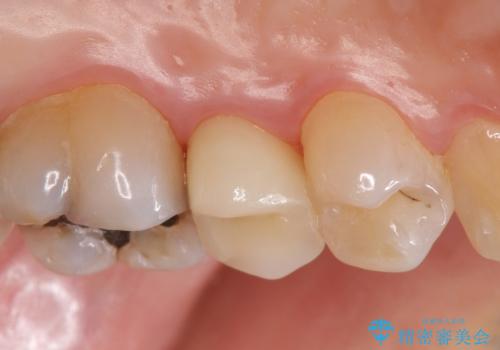

頬側の樹脂及び銀歯を除去後、オールセラミッククラウンにて補綴を行いました。

今回用いたオールセラミッククラウンはジルコニアフレームという白い素材の上にセラミックを盛っているため、審美性が非常に高いのが特徴です。

また、ジルコニアは人工ダイヤモンドの材料にも使われているほど高い強度を持っており、そのためオールセラミッククラウンは審美性だけでなく、奥歯やブリッジの補綴も可能とするクラウンです。